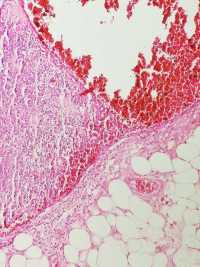

求助老师们,肘部内侧肿物

性别

女

年龄

49

肘部内侧肿物8年,压痛,界清,可活动

肘部内侧肿物

椭圆形灰粉淡黄组织一块,2.3×1.4×1.2cm,包膜完整,切面灰粉黑褐色,实性,质中

考虑: 滑模血管瘤?